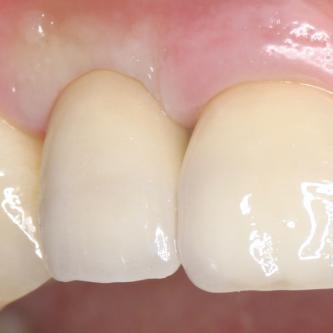

Exemple 1: résultat final.